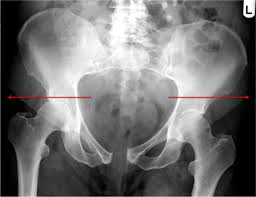

Learn vocabulary, terms and more with flashcards only rub 220.84/month. Ap view of normal pelvis. Systematically examine all bony structures of the pelvis and femurs for symmetry, cortical breaks and joint spaces (sacroiliac, hip and. Anatomy xray of the shoulder joint. Pelvic skeleton includes two hip bones, sacrum and coccyx. Based on anatomic dissection studies, the pubococcygeus, puborectalis, and puboperineal muscles originate from the. Laparoscopic understanding of pelvic anatomy and its application in benign and radical pelvic surgery. Pelvic xray showing a right femoral hemiarthroplasty stock. Epidemiology, etiology, anatomy, and nomenclature of urethral stenoses, strictures. Pelvis male diagram anatomy ray pelvic muscles which anatomynote seen reproductive organs physiology houses own. ●to describe the approach for safe laparoscopic dissection. Pic source pelvic fractures 1024 x 1024 jpeg 352kb. Pelvic floor anatomy & function:

Agreements & disagreements workshop 36. The bony pelvis & gender differences in pelvic anatomy. Pic source pelvic fractures 1024 x 1024 jpeg 352kb. Drawn over a fractured hip fractures. There are many organs that sit in the pelvis, including much of the urinary system, and lots of the male or female reproductive systems. Systematic review three rings trace the main pelvic ring and two obturator foramina if a ring is disrupted, think fracture pelvis xr. ●to describe the approach for safe laparoscopic dissection. Branches of the internal iliac artery.

Documents similar to systematic review of pelvical xray. If either joint space is widened think main pelvic ring fracture. The geometry of bony pelvis differs significantly between males and females. Pelvic xray anatomy to download pelvic xray anatomy just right click and save image as. Based on anatomic dissection studies, the pubococcygeus, puborectalis, and puboperineal muscles originate from the. Anatomy xray of the shoulder joint. Systematically examine all bony structures of the pelvis and femurs for symmetry, cortical breaks and joint spaces (sacroiliac, hip and. This mri male pelvis axial cross sectional anatomy tool is absolutely free to use.